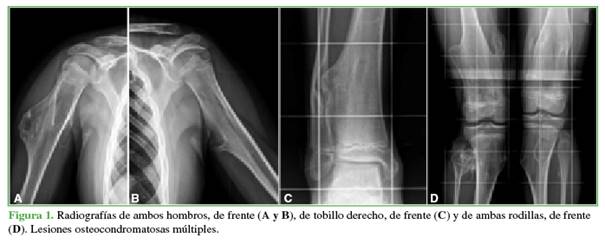

Tras ser derivada al Servicio de Patología de Columna Vertebral debido a un hallazgo incidental de osteocondroma cervical en una tomografía computarizada (TC) de rutina, en mayo de 2020, la paciente no tenía síntomas cervicales. El examen neurológico reveló hallazgos normales, con reflejos presentes y signos negativos de Hoffman, clonus y Babinski. En la TC de columna cervical, se visualizó un osteocondroma ubicado en la lámina izquierda de C4, con extensión hacia el canal espinal (Figura 2). Además, se observó un osteocondroma pediculado en la pared posterior de T1, también con extensión hacia el canal espinal, junto con un osteocondroma en el proceso espinoso de C2. La resonancia magnética (RM) subsecuente de columna cervical confirmó la presencia del osteocondroma en la lámina izquierda de C4, que causaba una reducción en el diámetro del canal y tenía una señal hiperintensa en las secuencias en T2 (Figura 3).

Los otros dos osteocondromas espinales detectados en la TC no provocaban un compromiso medular según la RM. Los potenciales evocados subsensitivos de las cuatro extremidades indicaron una disminución en la amplitud. Ante este cuadro clínico, se decidió someterla a una descompresión cervical posterior y la resección del arco posterior de C4 sin instrumentación (Figura 4).